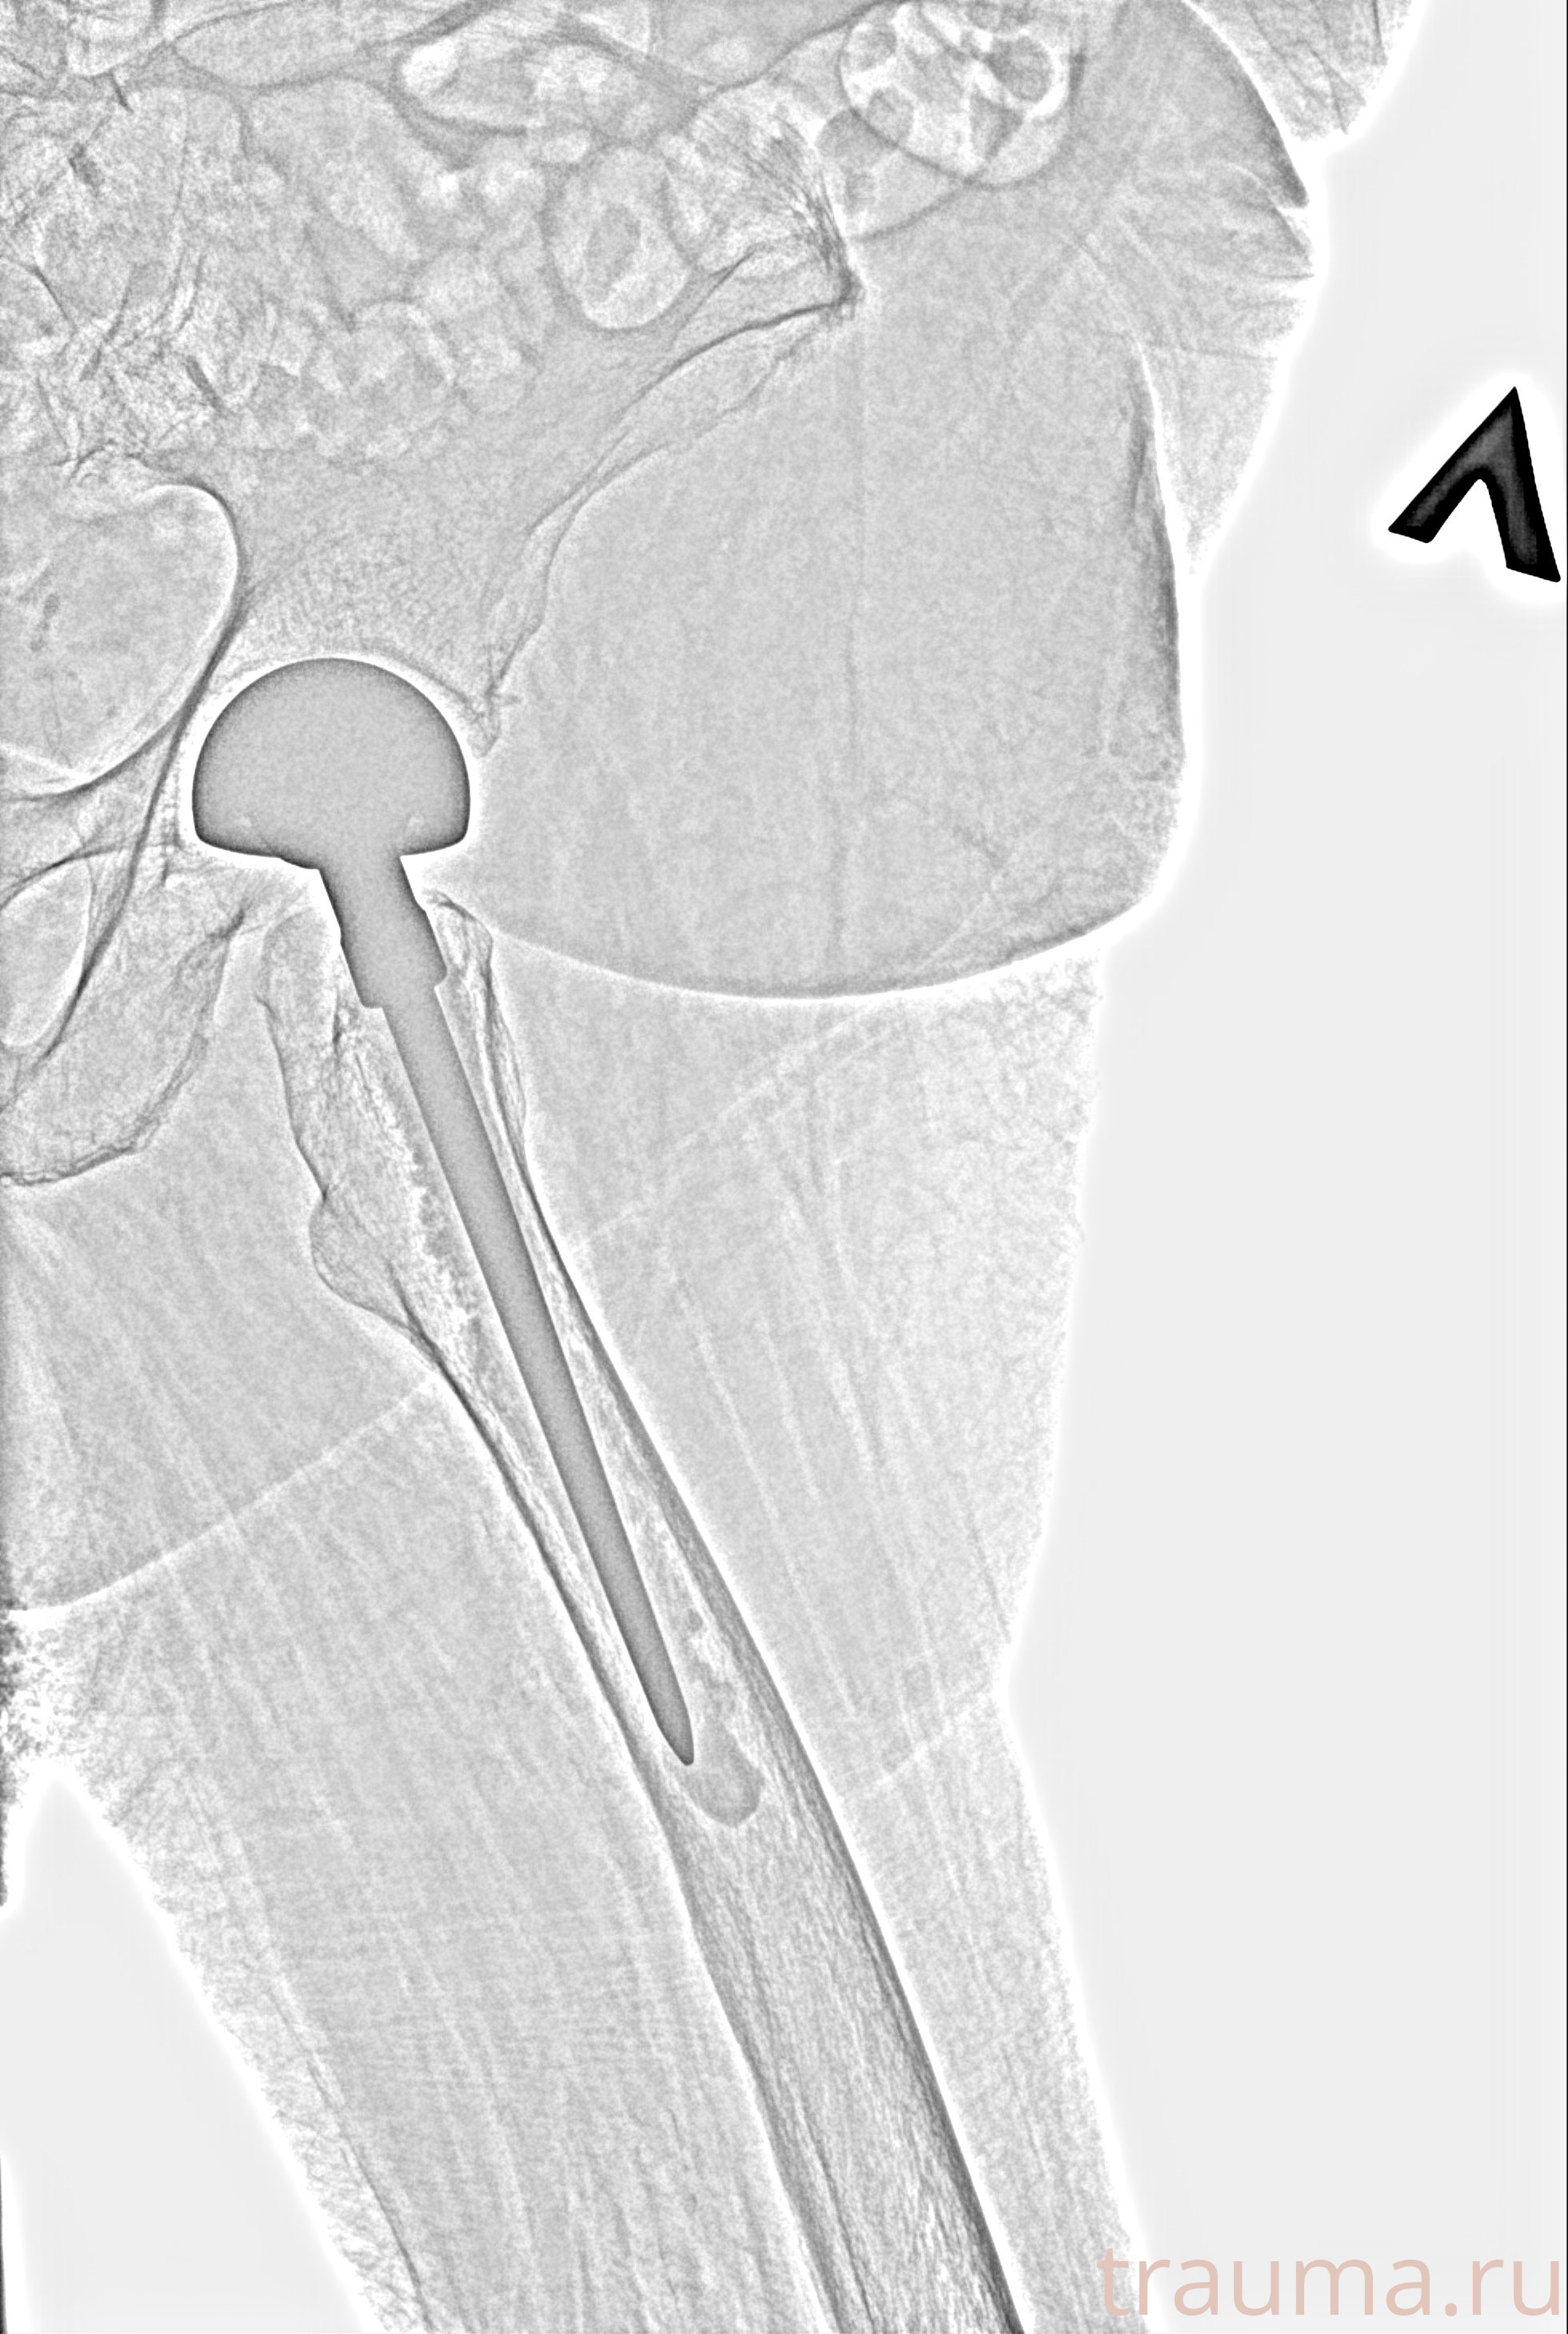

Рентген на дому: по вашему адресу приезжает врач-рентгенолог, травматолог-ортопед с мобильным рентгеновским аппаратом, проводит диагностику травмы или заболевания, делает необходимые рентгенограммы, дает рекомендации по дальнейшему лечению. Получить качественные снимки в домашних условиях возможно благодаря уникальной методике, разработанной МосРентген Центром для института  Склифосовского